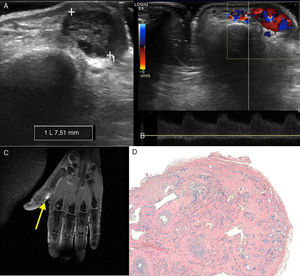

Presentamos el caso de una paciente de 59 años, que consultó por presentar una lesión nodular, de tonalidad azulada, ligeramente dolorosa, localizada en el tejido celular subcutáneo adyacente a la articulación metacarpofalángica del primer dedo de la mano izquierda. Se solicitó ecografía de partes blandas (figs. 1A y B), en la que se observó que la lesión presentaba un flujo vascular turbulento en su interior, con un patrón arterial de baja resistencia y una rama arterial aferente que se dirigía a la lesión descrita. También se realizó RM (fig. 1C), identificándose la lesión como hiperintensa (flecha) en secuencia potenciada en T2 con saturación de la grasa. Estos hallazgos sugirieron una lesión vascular, se reinterrogó a la paciente sobre antecedente traumático y se confirmó este, por lo que se planteó la posibilidad de seudoaneurisma postraumático o hemangioma. Se llevó a cabo resección quirúrgica y análisis anatomopatológico (fig. 1D), que demostró numerosos espacios vasculares revestidos por un endotelio sin atipias sobre un estroma con papilas hialinizadas. El estudio inmunohistoquímico con el anticuerpo anti-CD34 confirma la diferenciación vascular de la lesión. El cuadro histopatológico corresponde a una hiperplasia endotelial papilar intravascular conocida también como hemangioma o tumor de Masson1,2.

A. Imagen de ecografía en modo B en la que se observa una lesión de 7’5 mm en las partes blandas de la vertiente medial del primer dedo de la mano. B. Imagen de ecografía Doppler espectral en la que se observa un patrón arterial de baja resistencia. C. Imagen de RM potenciada en T2 con saturación grasa, la lesión es hiperintensa (flecha). D. En el análisis anatomopatológico la tinción hematoxilina eosina mostró numerosos espacios vasculares revestidos por un endotelio sin atipias sobre un estroma con papilas hialinizadas.